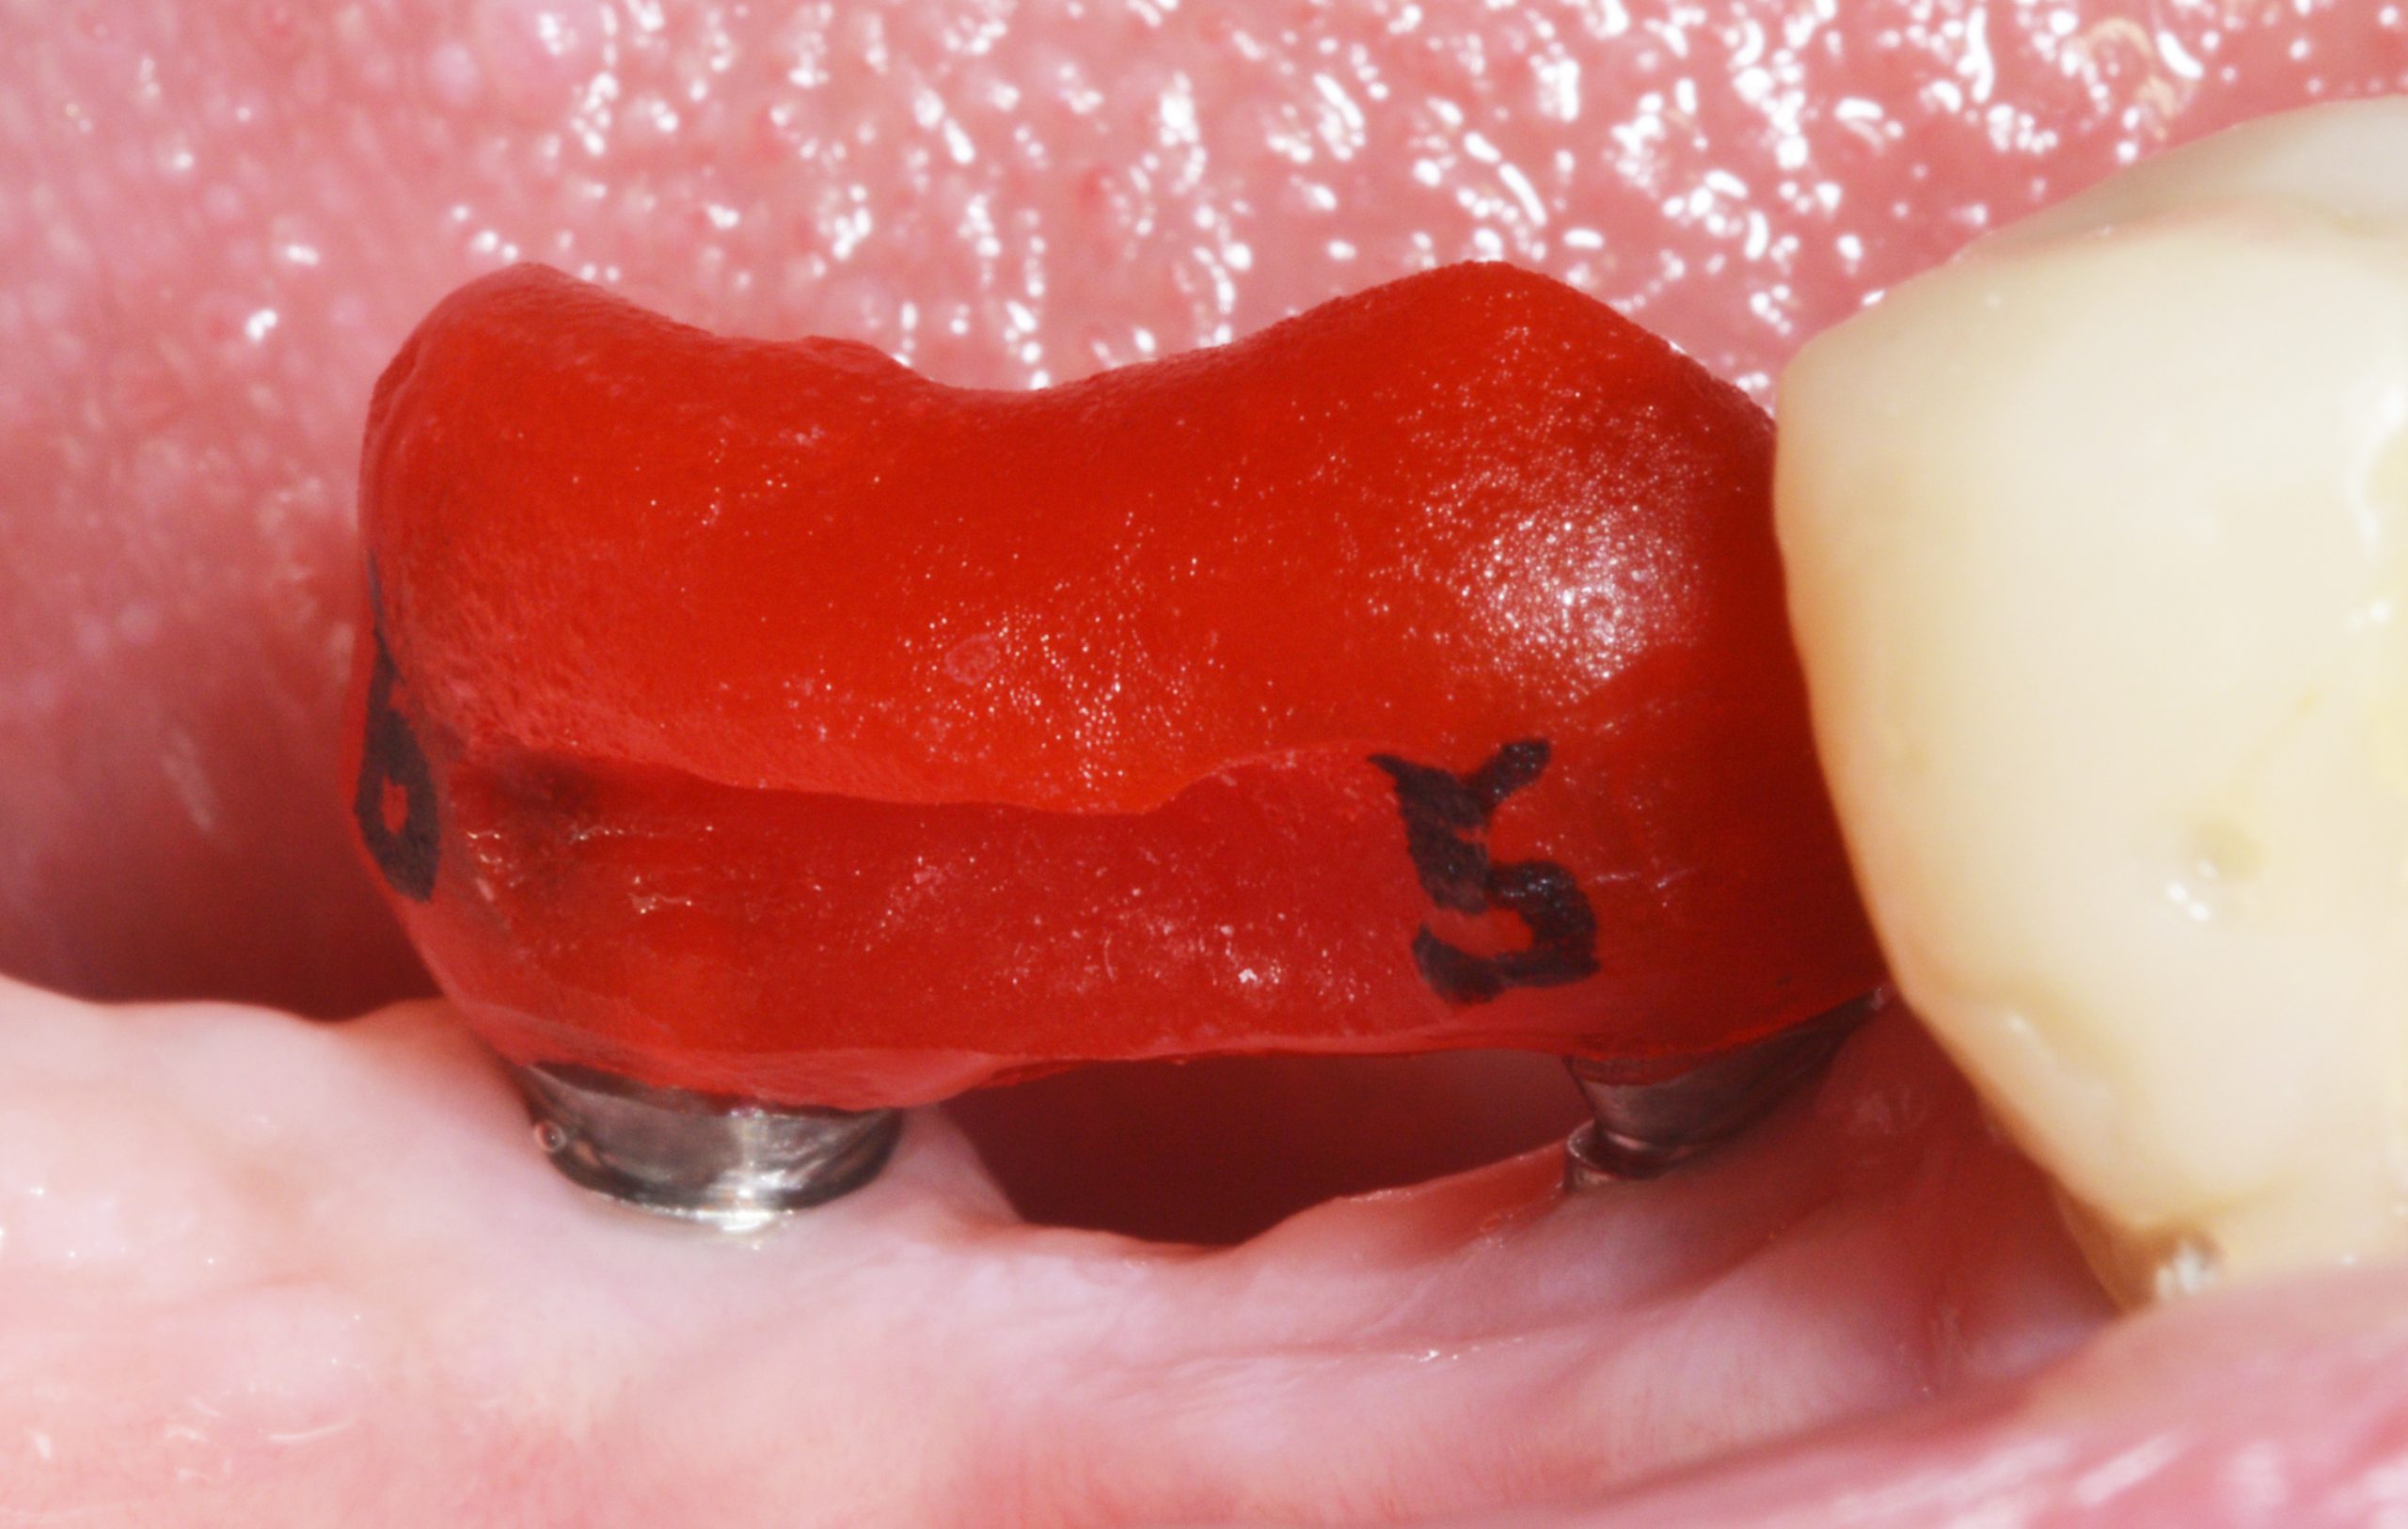

In the course of the treatment, the defective crown 44 was also redesigned. The implant fit was verified with an implant control splint to be on the safe side due to the very slight distortion that can never be ruled out when taking the impression.

Intraorally, the splint can be fitted tightly but without tension.